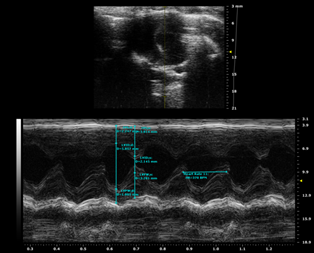

观察指标:心脏B超检测 EF及左心室舒张末内径(LVEDD)和左室收缩末内径(LVESD);Masson染色或天狼星红染色观察心肌组织纤维化情况,伊文思蓝-TTC染色观察梗死面积;HE染色观察病理;ELISA检测血清中的TNF-α、IL-1β及IL-6等炎症因子。

图注:TAC模型心电图

图注:TAC模型4周后心电图